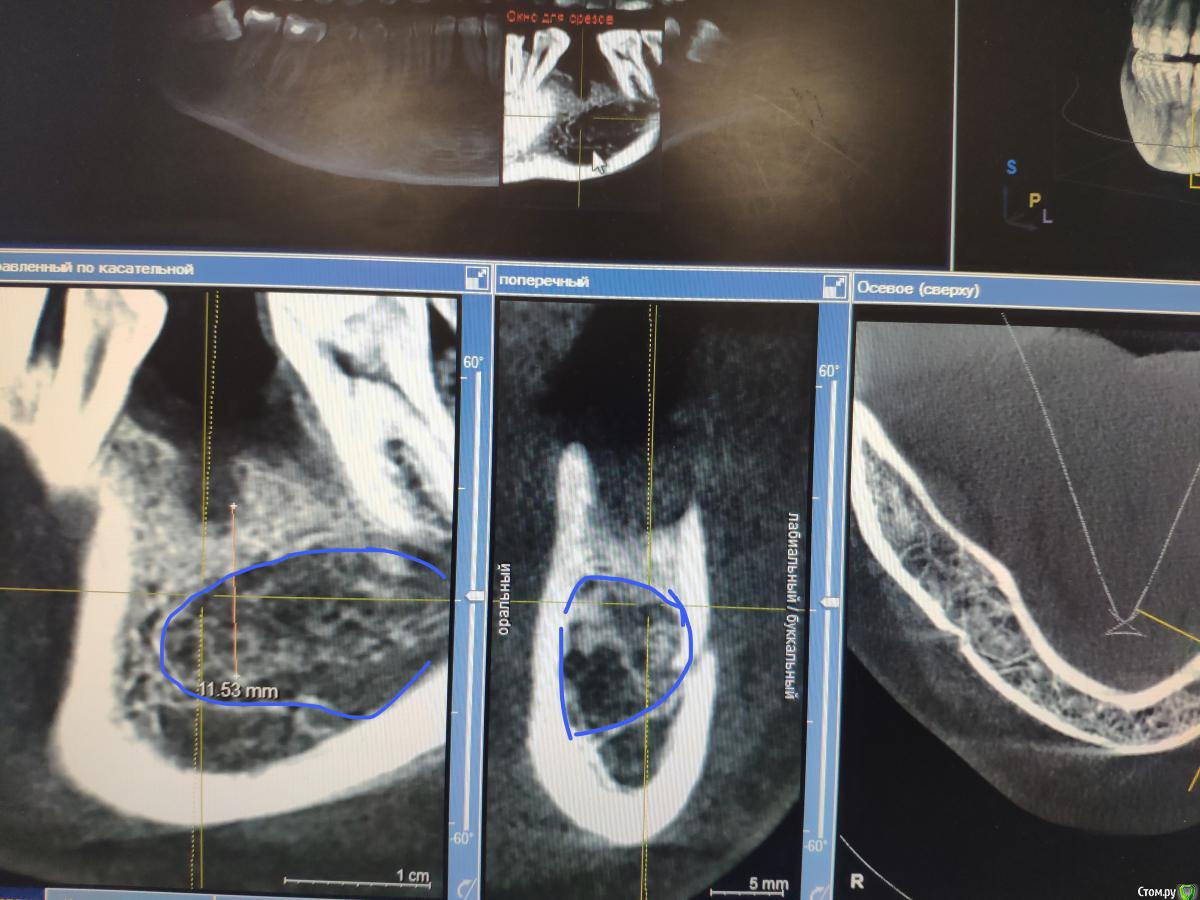

Женька Опубликовано 9 июня, 2020 Поделиться Опубликовано 9 июня, 2020 Тоже спрошу, чтобы не плодить темы.Пришла вот такая пациентка, удаление 28 февраля 2020. Думаю, что ничего страшного и можно ставить не взирая на образование, по крайней мере, мне видится, что это не апексы... тень думаю, потому, что лунка всё еще в стадии заживленияЧто скажете, коллеги? Ссылка на комментарий

Irouil Опубликовано 9 июня, 2020 Поделиться Опубликовано 9 июня, 2020 Как минимум один кусочек чего-то белого на последнем срезе есть Можно ещё прицелку посмотреть. А что с анамнезом? Ссылка на комментарий

Женька Опубликовано 9 июня, 2020 Поделиться Опубликовано 9 июня, 2020 Как минимум один кусочек чего-то белого на последнем срезе есть Можно ещё прицелку посмотреть. А что с анамнезом?В анамнезе у бабушки Cr желудка.Прицела к сожалению нету пломбировочный материал? мне кажется он В остальном считает себя здоровой, по врачам не бегает, на учётах не состоит. Во время удаления (удалял не я) делали прицелы после, и тоже увидели это образование (со слов пациентки). Ссылка на комментарий

Fin Опубликовано 9 июня, 2020 Автор Поделиться Опубликовано 9 июня, 2020 В анамнезе у бабушки Cr желудка.Прицела к сожалению нету пломбировочный материал? мне кажется он В остальном считает себя здоровой, по врачам не бегает, на учётах не состоит. Во время удаления (удалял не я) делали прицелы после, и тоже увидели это образование (со слов пациентки).Удаление 28 было, а когда сделано КТ?. По мне да, лунка в стадии заживления, если вы про дистальное образование то это одонтома, а вот на верхушке гребня что то есть. Думаю что ничего страшного,сделаете прицельный снимок перед имплантацией и если что во время операции уберете. Ссылка на комментарий

red_butler Опубликовано 9 июня, 2020 Поделиться Опубликовано 9 июня, 2020 Что скажете, коллеги? я бы удалил и возможно на гистологию отправил 2 Ссылка на комментарий

Женька Опубликовано 9 июня, 2020 Поделиться Опубликовано 9 июня, 2020 Удаление 28 было, а когда сделано КТ?. По мне да, лунка в стадии заживления, если вы про дистальное образование то это одонтома, а вот на верхушке гребня что то есть. Думаю что ничего страшного,сделаете прицельный снимок перед имплантацией и если что во время операции уберете.Кт от 8 июня. я бы удалил и возможно на гистологию отправилИз-за анамнеза родословной? Ссылка на комментарий

red_butler Опубликовано 9 июня, 2020 Поделиться Опубликовано 9 июня, 2020 Кт от 8 июня. Из-за анамнеза родословной?Нет, новообразование имеет оболочку, не хотелось бы удалять имея там имплант 1 Ссылка на комментарий

Женька Опубликовано 9 июня, 2020 Поделиться Опубликовано 9 июня, 2020 Записал срезы Кт, вижу что-то похожее на корень с ярким материалом в области края гребня. И образование, по плотности как кортика. + лунки заживающие. Ссылка на комментарий

red_butler Опубликовано 9 июня, 2020 Поделиться Опубликовано 9 июня, 2020 https://youtu.be/1pW5wBBAbls Записал срезы Кт, вижу что-то похожее на корень с ярким материалом в области края гребня. И образование, по плотности как кортика. + лунки заживающие.Похоже на корень. А есть снимки до удаления? И настораживает, зачем коллеги делали rg после удаления.., Ссылка на комментарий

Женька Опубликовано 9 июня, 2020 Поделиться Опубликовано 9 июня, 2020 Похоже на корень. На верхушке гребня с ярким рентгеноконтрастным материалом? или где-то в другом месте? А есть снимки до удаления? Была вроде ОПТГ, попробую вытянуть у пациентки.И настораживает, зачем коллеги делали rg после удаления..,Именно из-за этого плотного образования. Ссылка на комментарий

Женька Опубликовано 10 июня, 2020 Поделиться Опубликовано 10 июня, 2020 А есть снимки до удаления? Можно ещё прицелку посмотреть. Прицелки нет, как я сказал, но есть ОПТГ до удаления, правда не лучшего качества... Ссылка на комментарий

Irouil Опубликовано 10 июня, 2020 Поделиться Опубликовано 10 июня, 2020 я бы удалил и возможно на гистологию отправилТут мне кажется верное решение Похоже на какую-то цементому не удалённую, но все же Ссылка на комментарий

Женька Опубликовано 10 июня, 2020 Поделиться Опубликовано 10 июня, 2020 Тут мне кажется верное решение Похоже на какую-то цементому не удалённую, но все жеВозможно меня неправильно поняли) у бабушки пациентки был Cr в анамнезе...Или разницы нет и не стоит имплантировать пока не уберу образование?Но тогда другой вопрос, как оптимальнее его вытащить? или не важно и всё равно придется аугментировать и ждать? Ссылка на комментарий

Irouil Опубликовано 10 июня, 2020 Поделиться Опубликовано 10 июня, 2020 Возможно меня неправильно поняли) у бабушки пациентки был Cr в анамнезе...Или разницы нет и не стоит имплантировать пока не уберу образование?Но тогда другой вопрос, как оптимальнее его вытащить? или не важно и всё равно придется аугментировать и ждать?Про бабушку я понял. Но если эта штука осумкована (а на орто до тоже так кажется), то вокруг импланта пойдёт расти ее капсула, а не кость. По крайней мере есть такой риск. Ну а на гистологию всегда лучше сдать, чем не сдать Ссылка на комментарий

Женька Опубликовано 10 июня, 2020 Поделиться Опубликовано 10 июня, 2020 Про бабушку я понял. Но если эта штука осумкована (а на орто до тоже так кажется), то вокруг импланта пойдёт расти ее капсула, а не кость. По крайней мере есть такой риск. Ну а на гистологию всегда лучше сдать, чем не сдатьРазницы крестально идти или вестибулярно особенной нет? Всё равно через аугментацию и отсроченно имплантировать? Ссылка на комментарий

Irouil Опубликовано 10 июня, 2020 Поделиться Опубликовано 10 июня, 2020 Сложно сказать. Наверное - крестально, там мягко, судя по снимку, да и дефект с лучшим прогнозом. Главное чтобы не слишком глубоко и узко для доступа было Ссылка на комментарий

Женька Опубликовано 10 июня, 2020 Поделиться Опубликовано 10 июня, 2020 Главное чтобы не слишком глубоко и узко для доступа былоИ если так, то придется расширять и копаться или добавлять вестибулярный доступ Ссылка на комментарий